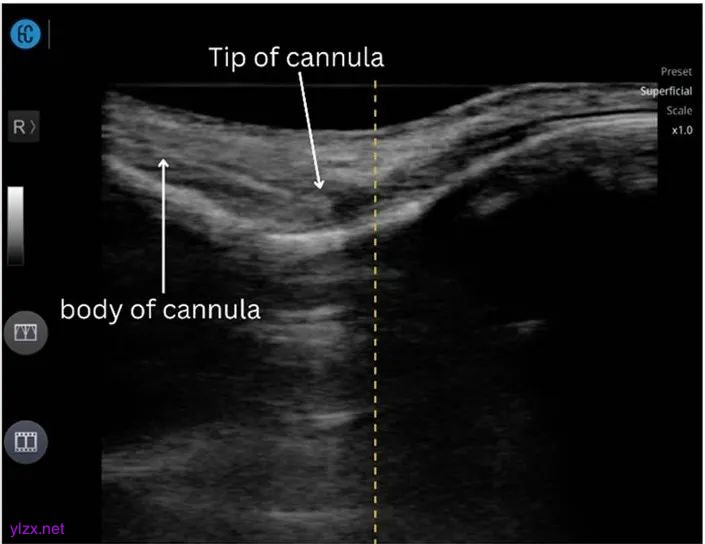

使用500 IU(1 mL)透明质酸酶通过25G、50 mm钝针进行超声引导下的透明质酸酸酶注射(图4)。注射后进行超声检查,以确保所有低回声区域都转变为棉质外观。

图4:使用25G、50mm钝针进行超声引导透明质酸酶注射。图像显示,在超声引导下,钝针尖端被引导到低回声区,将透明质酸酶输送到残留的透明质酸中。使用平面内技术来可视化钝针路径。

她接受了500 IU透明质酸酶(1 mL)的治疗,该酶通过平面内超声引导注射技术,使用25G、50 mm的钝针输送(图6)。将透明质酸酶直接注射到残留的透明质酸区域,确保超声波上识别的低回声区转变为棉状外观,表明对填充剂的酶作用成功。

图6:使用25G、50mm钝针进行超声引导透明质酸酶注射。图像显示,在超声引导下,钝针尖端被引导到低回声区,将透明质酸酶输送到残留的透明质酸中。使用平面内技术来可视化钝针路径。注意到钝针产生的混响伪影。